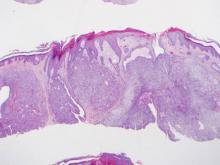

Histopathologic examination of a CCH generally reveals an unencapsulated and circumscribed neoplasm in the mid or upper dermis with occasional extensions into the subcutaneous fat (Figure 2). The tumor typically presents with 2 types of cells: (1) round, fusiform, or polygonal cells with vesicular nuclei and eosinophilic cytoplasm, and (2) cells with clear cytoplasm and basophilic, often eccentrically located nuclei.6 Ducts are scattered within the neoplasm and are lined by a layer of cuboidal cells that can be highlighted on carcinoembryonic antigen and epithelial membrane antigen immunostaining.6 The tumor cells themselves are highlighted on cytokeratin AE1/AE3 staining.